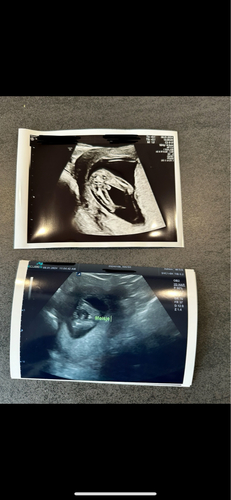

Haha wij hebben dit ook gehad maar dan al met 14 weken. En beide echo’s toevallig op dezelfde dag. Geloof dat het voor jou nog meer een omschakeling is omdat je het al een tijdje dacht. Ik vind beide echo’s indd wel duidelijk😅 gek he, misschien toch de navelstreng toevallig geweest

Goh, het lijkt inderdaad écht een jongetje op de echo van 16 weken! Dat ze het met 16 weken zelfs verkeerd kunnen zien!

Ohhh nou dat is schakelen! Ik ga nu zelf ook ineens denken ‘wat als dat bij mij ook zo is..’. Ook met 16 weken geslachtsbepaling gedaan en exact zo’n foto als die van jou (en ook een jongetje!). Over 2 weken 20weken echo , ben benieuwd. Maar zal vast niet heel vaak voorkomen dat het verkeerd gezien wordt denk ik?!

hier met 15 weken echo gehad liet ze ook een piemeltje zien en zij ze een jongen 1 week later nog een echo gehad en toen zij ze ik kan toch echt niks meer zien het wordt een meisje😅 ik wacht nu gewoon af tot de 20 weken echo en hoop dan meer duidelijkheid te hebben. Ik heb al een zoontje en dochtertje dus wat het ook wordt met alle liefde welkom🥰

Wat bizar! Het lijkt zo duidelijk op de eerste foto. Ik ga nu ook twijfelen aan onze geslachts bepaling 🥲 heb bijna alle kleertjes al aangeschaft (kon me niet inhouden) dus hoop dat het klopt hahahahaha

oh nee. wat een omschakeling dan ineens. Dit is dus echt mijn grootste angst. Daarom wilde ik het bij de eerste niet weten. Nu heel sterk het gevoel gehad van een meisje. Bij geslacht echo (15+4) werd een jongentje gezien. Beetje zelfde foto als jou. Volgende week woensdag heb ik 20 weken echo. Daar gaan we het sowieso navragen. Daarnaast zijn de verloskundige heel duidelijk. Ik denk het zeker te weten, maar raad je wel aan tot 20 weken niks te kopen. 😅

Jaaaa hier ook. We hebben al een dochtertje en had echt een sterk voorgevoel voor een jongen. Het duurde even voor ze iets vond, want er zaten steeds 2 voetjes voor, hij zat in kleermakerszit 🤣 Maar het was idd vrij duidelijk, maar dat is de echo van TS ook!! 😵💫🤣 Nou moet ik zeggen dat die van ons wel echt zo'n vorm heeft van een balzakje en pieletje hahahaha maar toch... Ik ben ook vrijwel direct gaan shoppen...😬